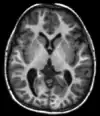

| استعادة الإنعكاس ضعيف السوائل | FLAIR | إيقاف إشارة السوائل بإعداد وقت الإنعكاس الذي يُصعف إشارتها | إشارة عالية في السكتات الدماغية الجوبية، والتصلب المتعدد، والنزيف تحت العنكبوتية، والتهاب الأغشية السحائية.[11] | ![]() | |

استعادة الإنعكاس ضعيف السوائل

يُمثل استعادة الإنعكاس ضعيف السوائل[34] تتابع نبضات استعادة الانعكاس، يُستخدم لإضعاف إشارة السوائل، ويُمكن استخدامه في تصوير الدماغ للإضعاف السائل الدماغي الشوكي لإخراج الآفات المحيطة بالبطينات، مثل لويحات التصلب المتعدد، كما يمكن قمع إشارة أي نسيج معين، من خلال الاختيار الدقيق لوقت الانعكاس (الوقت بين نبضات الانعكاس ونبضات الإثارة).